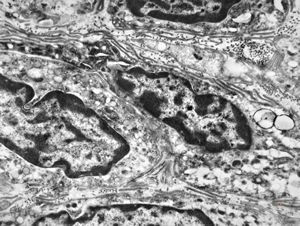

F,41y. | synovial metaplasia - capsule of implantate